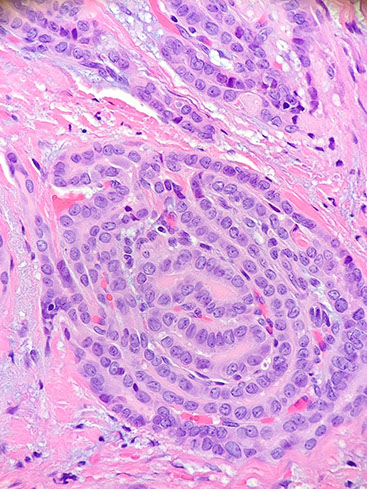

- A characteristic histologic feature of this entity is the presence of squamoid morules, which are small

collections of squamoid cells without keratinization arranged in a whorling pattern.

CMTC with squamoid morules